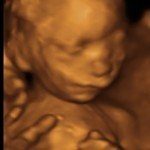

4D/5D/HD Ultrasound Gallery

Gallery